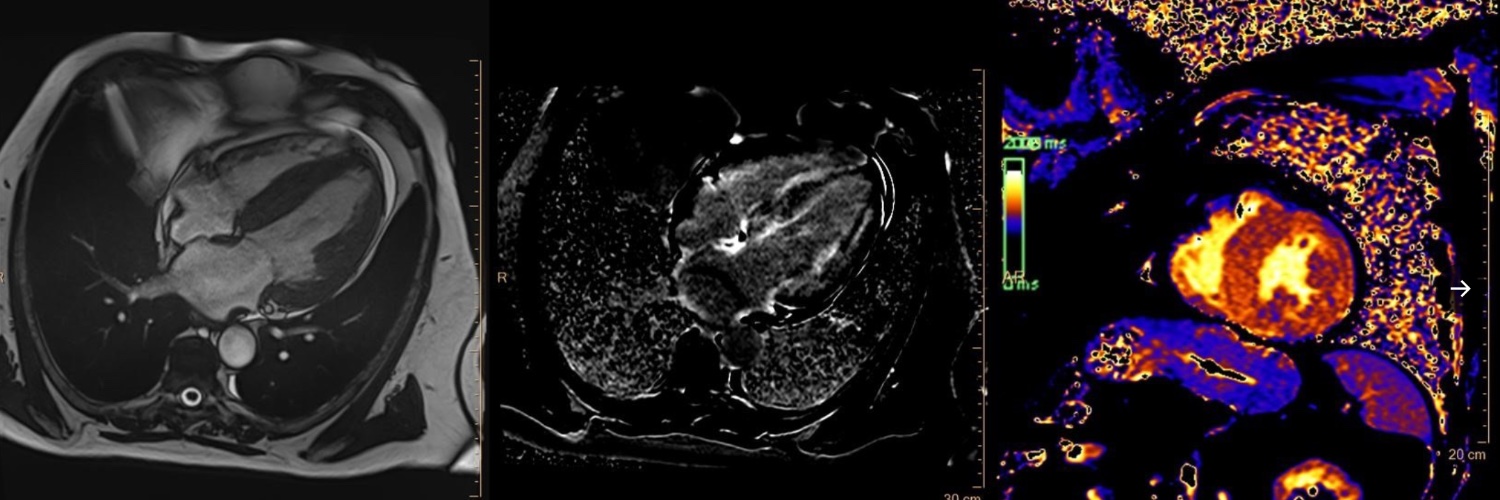

Just published on @ESCHeartFailure our meta-analysis on the prognostic role of T1 mapping in NIDCM. Both T1 mapping and ECV were associated with increased risk of the primary endpoint of MACE and the secondary endpoint of heart failure and arrhythmic-related events.